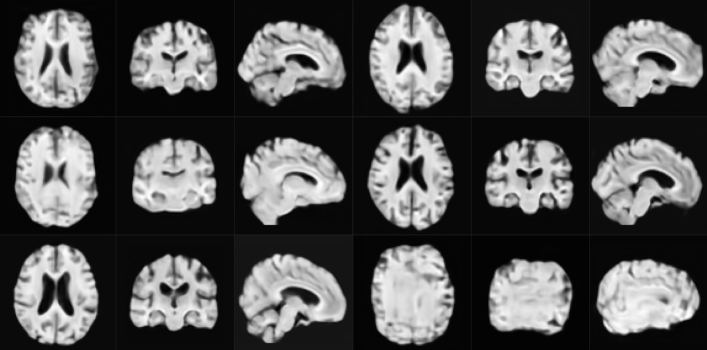

Qualitative analysis of the compared methods reveals that samples from VAE are not anatomically correct in many cases and display regions that appear scrambled. WGAN generates anatomically viable samples, however in many of them the cortical folds do not follow the anatomical structure. Additionally, as in VAE, samples exhibit regions where artifacts are dramatically different from the rest of the volume. Samples from our model are the most anatomically correct due to starting from the fixed template. However, the samples occasionally have a wavy visual quality due to improperly generated random deformation fields at finer scales. We furthermore observe a lack of sufficient topological diversity in the cortical folds. Samples for each of the above methods are shown in Section A of Supplementary Material.